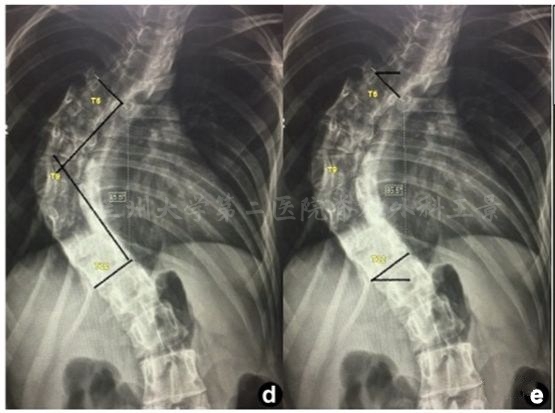

如法炮制,拍照测量脊柱侧弯Cobb角

为方便演示,照片标注上、下端椎终板连线

旋转照片使终板连线和网格线重叠

读出上、下端椎的倾角绝对值

相加后就是Cobb角

这就叫

端椎倾角法快速测量Cobb角